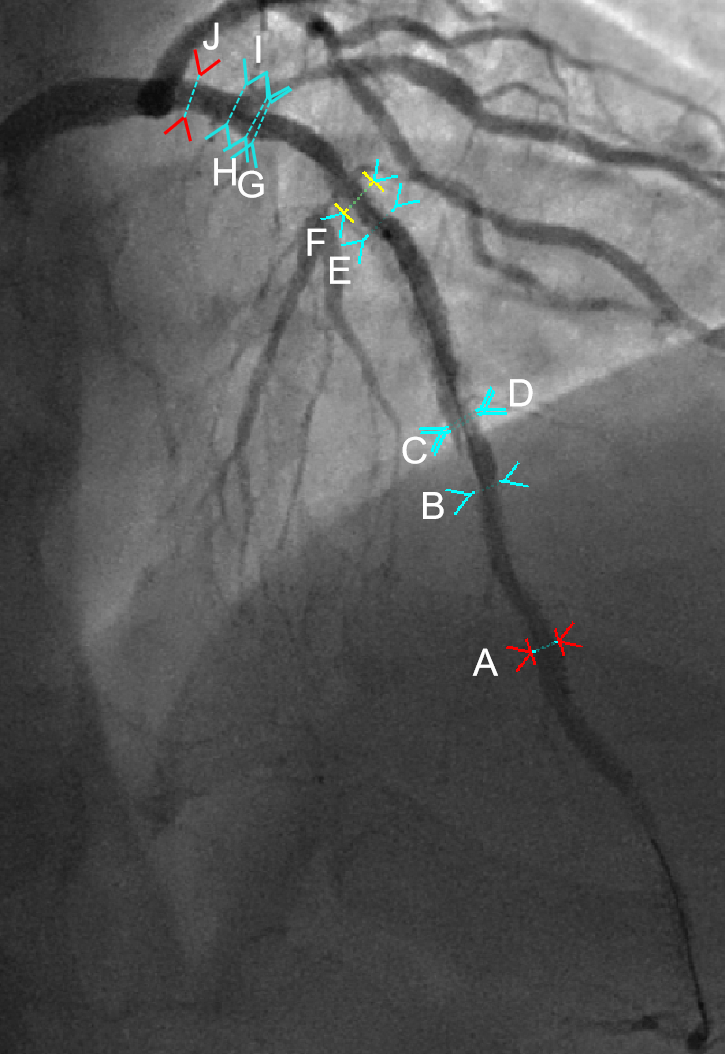

图注:

图中E-G段:3.0*20mm支架

图中H-I段:2.3mm:D1的2.25*15mm支架在开口部位伸入LAD的支架梁

图中J部位:LAD近端,接近180°脂质斑块,且有巨噬细胞侵润

此次心梗在图中E-F段,刚好是三层支架部位,有支架贴壁不良的情况,且有可能的斑块破溃存在。

图中B-C段,支架边缘夹层,因此,选择短支架覆盖

图中E-F段,此次心梗部位,已有三层支架,且主要为均质型新生内膜增生,选择DCB,由于该处远近均为支架段,且存在不同程度的ISR,因此,选择长药球全程覆盖。